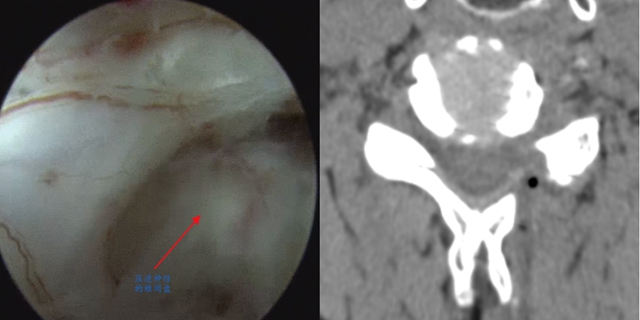

“患者基础疾病多,开放手术风险较高。”面对患者的复杂情况,谢明忠副主任医师带领团队进行反复讨论,9月10日,由谢明忠副主任医师主刀,戚力升主治医师、冯怡主管护师协助,采用颈椎椎间孔镜技术——通过直径仅7毫米的小孔,将椎间孔镜插入病变部位,在可视镜下精准定位并摘除压迫神经的髓核组织,整个过程仅用时2小时。

传统颈椎前路颈椎手术切口(约5cm) 颈椎椎间孔镜手术切口(<1cm)